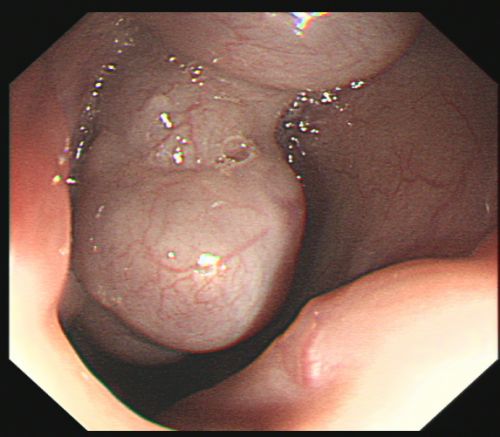

胃镜下可以看到食管静脉重度曲张。

经过积极抢救,易某病情稍稳定,被转入综合内科病房继续治疗。入院进一步完善胃镜检查结果提示:食管静脉重度曲张,加上血管壁极薄,随时可能破裂大出血。